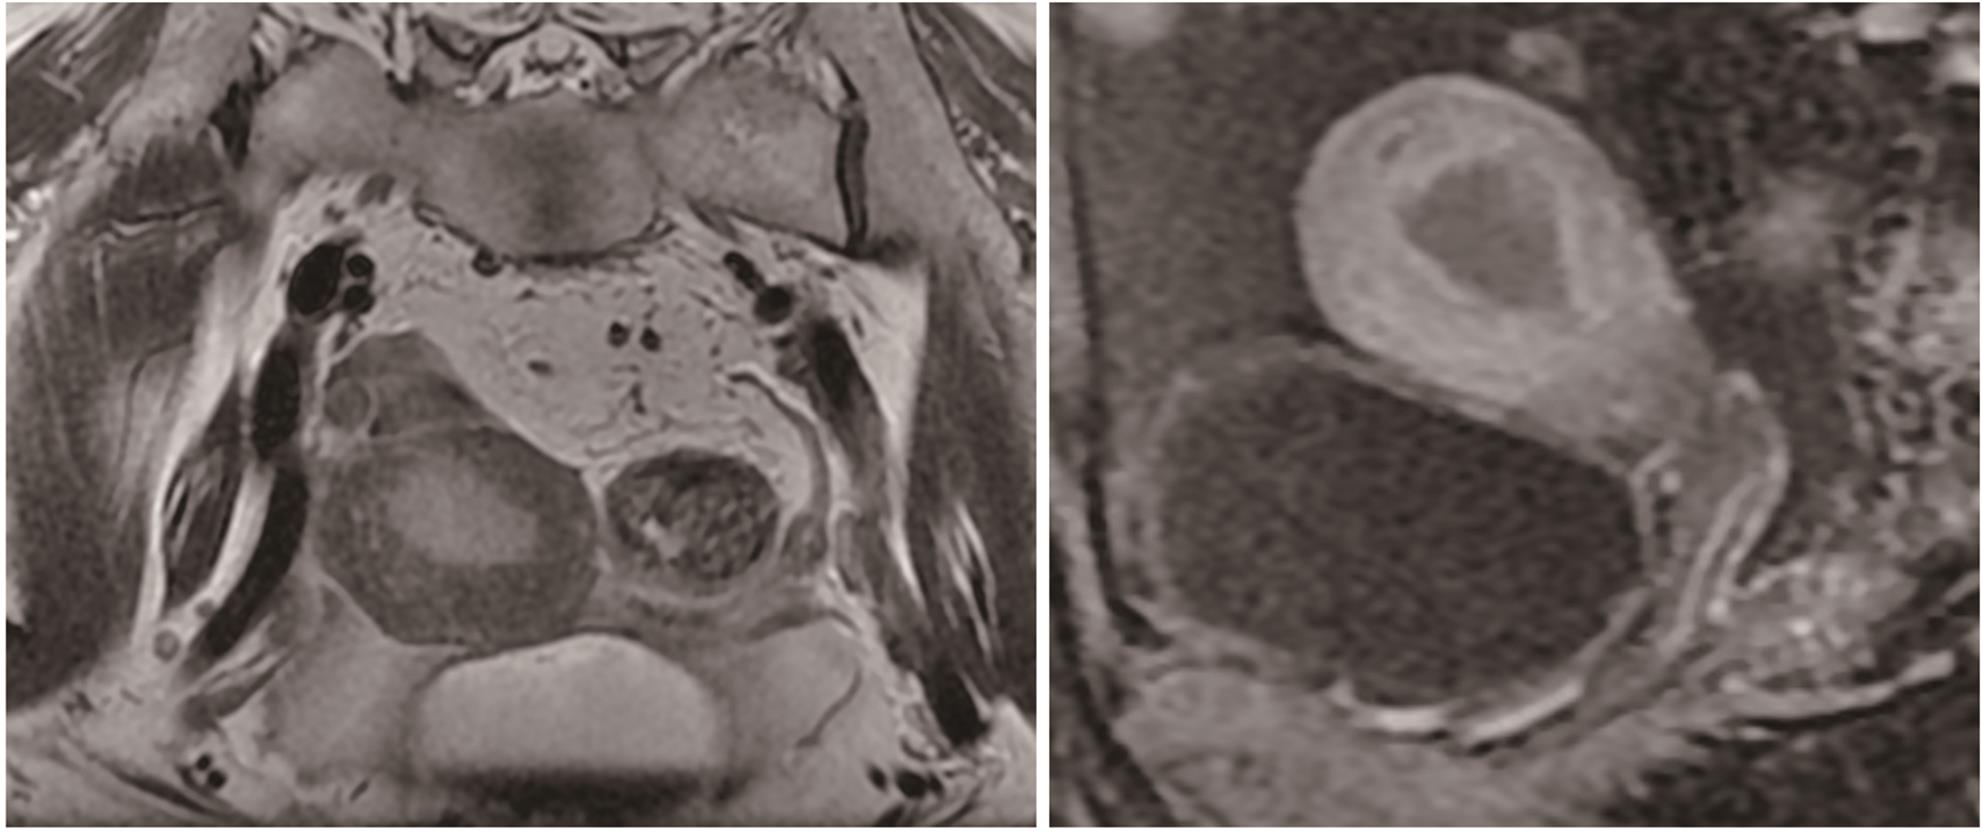

Construction of pancreatic cancer organoids and their sensitivity to chemotherapy drugs

Jingyu WANG, Rong HUANG, Yan LU, Ziran CHEN, Xiaojie ZHANG, Hu REN, Nan ZHANG, Dongbing ZHAO, Wei SONG, Xingguang ZHANG

2024, 40(9): 1853-1858. DOI: 10.12449/JCH240921

Abstract(1526) HTML (281) PDF (3800KB)(107)

Abstract:

Objective  To construct and identify a patient-derived organoid model, and to investigate the sensitivity of chemotherapy drugs using this model.  Methods  Pancreatic cancer cells were obtained from the surgical specimens of two female patients with a confirmed diagnosis of pancreatic cancer after tumor tissue digestion, and then the cells were inoculated into a culture dish using matrigel for three-dimensional culture. Paraffin sections were prepared for HE staining and immunohistochemical staining and were compared with the parent tumor tissue to determine whether the histopathological features of the tumor in vivo were preserved. The pancreatic cancer organoids were treated with seven chemotherapy drugs at different concentrations; Cell Titer-Glo®3D reagent was used to measure cell viability, and the results of drug sensitivity were analyzed.  Results  Two patient-derived pancreatic cancer organoids were successfully constructed, and HE staining and immunohistochemical staining showed that the pancreatic cancer organoids had consistent histopathological features with the tumors of the corresponding patient. Both pancreatic cancer organoids were more sensitive to gemcitabine monotherapy and the combination of oxaliplatin+SN38+fluorouracil, and patient 1 was more sensitive than patient 2. There were individual differences in the response to drugs between the organoids from different patients.  Conclusion  The pancreatic cancer organoid model successfully constructed in this study can reflect the histological classification of parent pancreatic tumors and can be used for in vitro chemotherapy drug sensitivity test, which is expected to provide a reference for clinical medication.